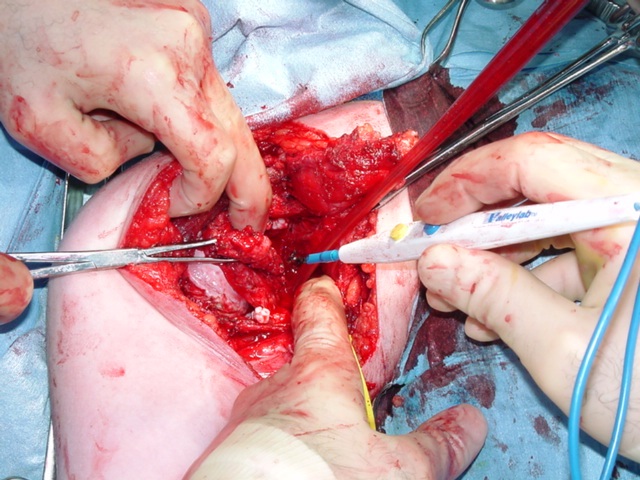

The treatment for synovial chondromatosis is the excision of the involved synovium and removal of the cartilage nodules (Fig. 6, Fig. 10-11). Recurrence is infrequent although it may recur in cases where removal is incomplete or synovium is affected diffusely. Malignant transformation is seen in less than 5% of the cases and is usually a low grade malignancy (synovial chondrosarcoma). Some papers suggest that degenerative arthritic changes still progress in the involved joint after surgical removal. In other words surgical removal may not prevent development of arthritis in the affected joint.

Fig 10 & 11. Intra-operative photographs demonstrate nodules of cartilage in the right shoulder joint (Fig. 10) and resection of the synovium (Fig. 11).